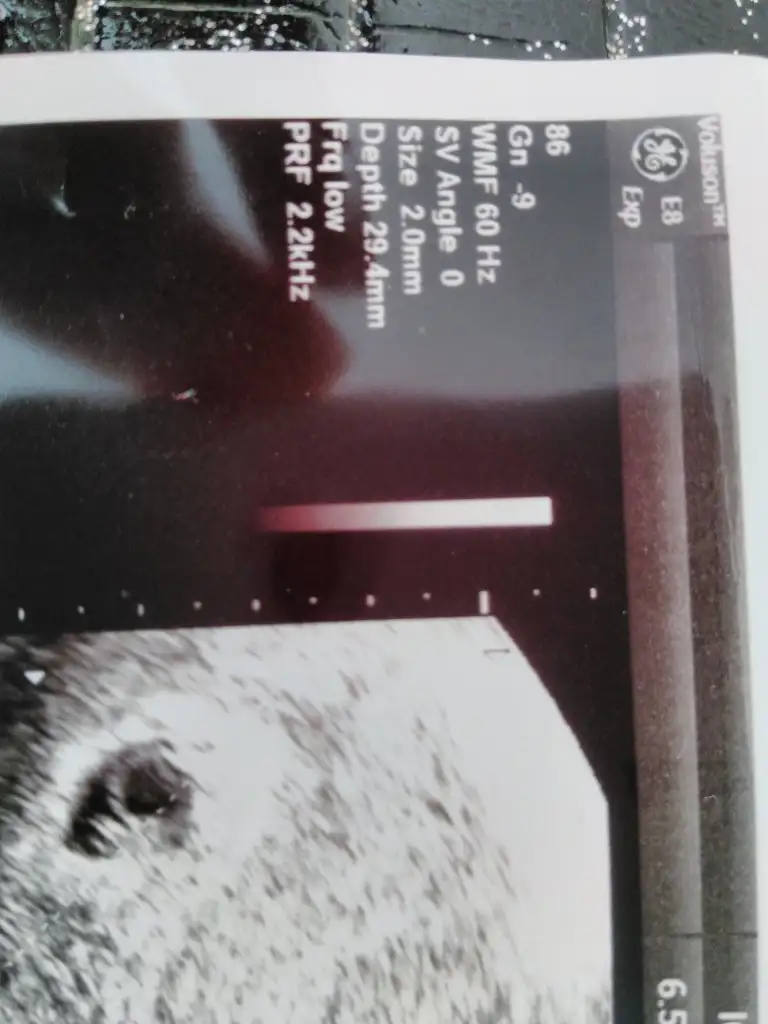

Ultrason fotoğrafını yuklesene canımİyi akşamlar kızlar ben ultrason kağıdında bulamıyorum dediğimiz ölçüleri içinizden biri kalemle işaretleyip buraya atabilir mi ultrason görüntüsünü

Canim benim sağ alt kısımda yazıyor benjm

Sagol canim kaydettim hemen onu da :)ultrason kağıdındaki kısaltmalar burada var kızlar, belki işinize yarar..

Ultrason kağıdında hafta ne yazıyor